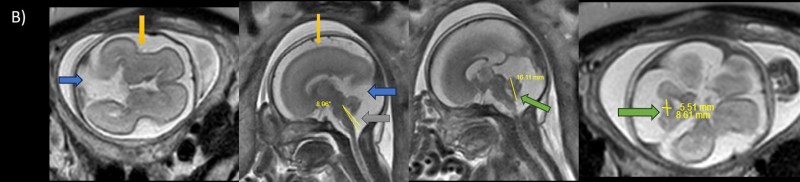

- A) USG incelemede serebral kortikal yapılar düzleşmiş (ok), gyrus sayısı azalmıştır (ok). Kalın ve ekojenik korteks mevcut olup korteks -beyaz cevher ayrımı silik görünümdedir. Posterior fossada ekstraaksiyel BOS mesafesi artmış görünümdedir (ok).